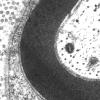

PERIPHERAL NEUROPATHY

2 NORMAL AXON